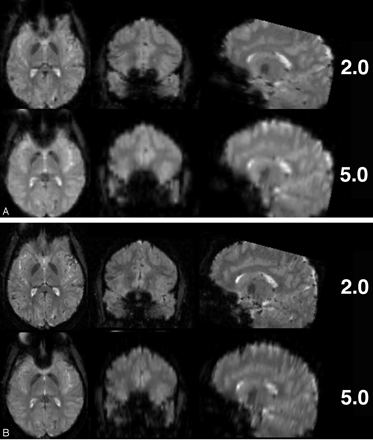

Further handles for optimizing echoplanar sequences to control for distortion effects at 3T are bandwidth and echo spacing (Fig 13). Reducing section thickness or increasing in-plane resolution (eg, 128 × 128 matrices) are additional options of note (Fig. 14A, -B).

Comparison of EPI with different voxel size regarding susceptibility artifacts at 3T. (A) Thinner sections (matrix, 64 × 64; TR 4500 ms; TE, 38 ms; bandwidth, 2170 Hz/pixel; FOV, 190 × 190 mm2; 53 sections; section thickness, 2 and 5 mm) and (B) smaller in-plane voxel sizes (matrix, 128 × 128; all other parameters same as in A) result in fewer susceptibility artifacts, especially in frontobasal regions.